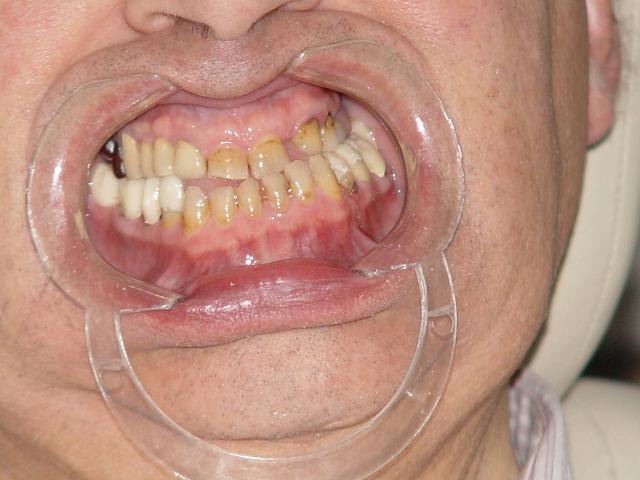

Un cas peu banal

la suite!!

Ma première idée de dire que l'occlusion était faussée par des contacts prématurés,des déviations des egressions,et qu'il fallait en premier lieu essayer de la retrouver dans une position plus conforme à la normale

L'usure des dents antérieures en est peut-être le résultat

en prenant les modèles en main, je m'aperçois que le patient excerce un bruxisme important entre face distale de 34 et face mésiale de 25. Autre bruxisme important ezntre 41 et 21 et aussi entre 32 et 22. Pour ma part malgré ce sentiment d'absence de perte de DV, je ne pourrai pas reconstruire une courbe et plan correct. Qu'en penses-tu ?

Je joins les photos des modèles avec l'occlusion que le patient semble donner.